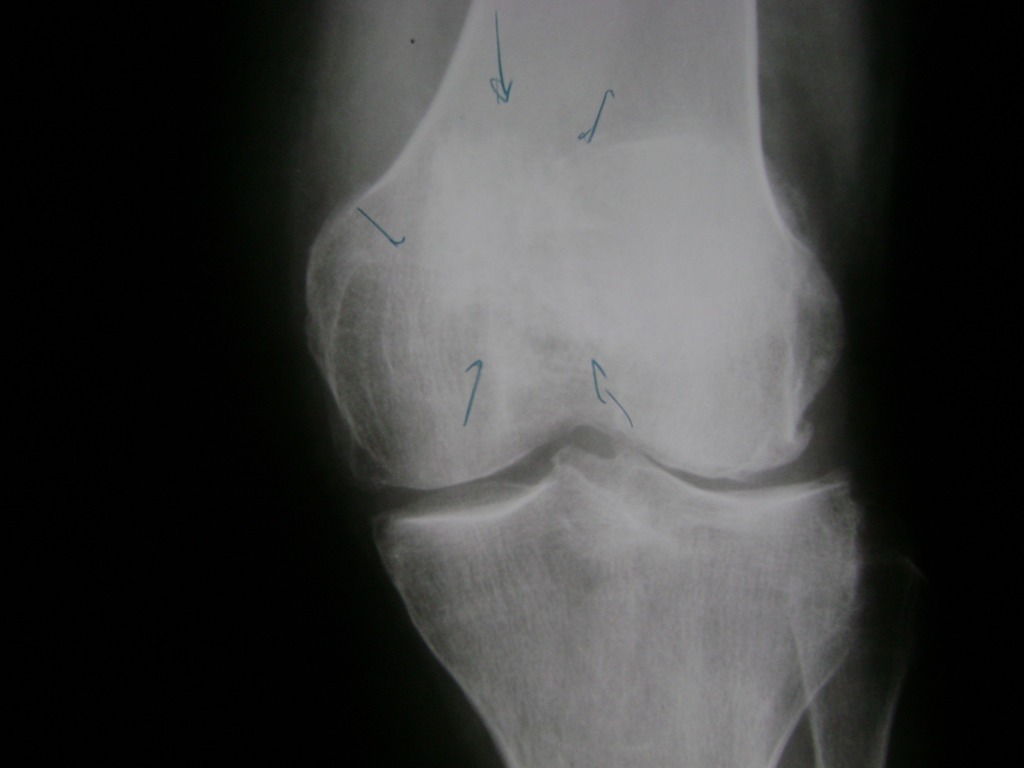

Cirugías de Húmero - Rodilla

La artroscopia de rodilla es un cirugía en el cual la estructura interna de la articulación es examinada ya sea para realizar un diagnostico o para realizar un tratamiento, este procedimiento se realiza utilizando un instrumento parecido a un pequeño tubo llamado artroscopio.